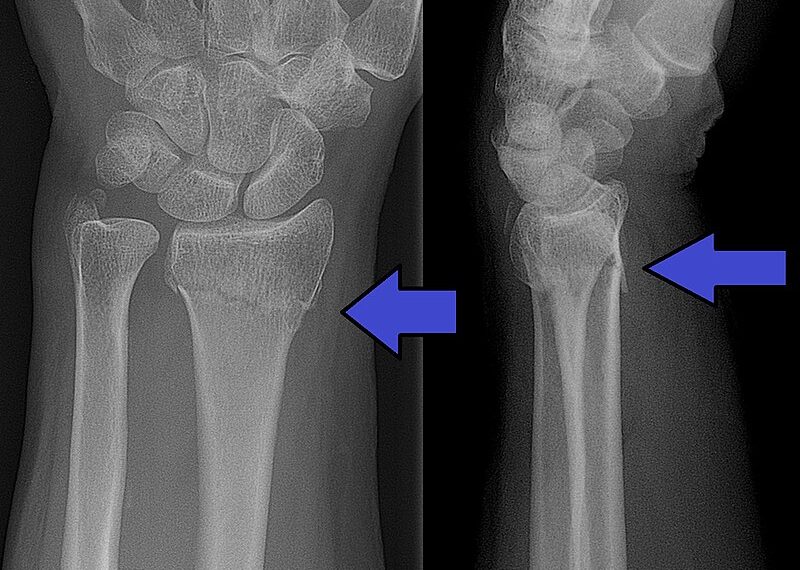

Hulpafdelingen van ziekenhuizen in de regio houden rekening met een flinke toename van het aantal patiënten dat binnenkomt met botbreuken door sneeuw en ijs.

De spoedeisende hulpposten zien nu nog geen stijging van beenbreuken of polsfracturen maar verwachten wel een flinke toename aankomend weekeinde, door verwachte ijspret en aanhoudende gladheid de komende dagen. Premier Rutte riep vorige week nog op voorzichtig te zijn op het ijs. Schaatsverwondingen zouden nog meer druk op de zorg kunnen leggen, die nog altijd overbelast is door de zorg voor coronapatiënten.

De tachtig Nederlandse spoedeisendehulpafdelingen signaleerden vorige week maandag toen het plotseling glad was wel extreme drukte. Artsen behandelden tot twee keer meer patiënten dan normaal. Zij waren bijna allemaal slachtoffer van de gladheid. Afdelingen hebben extra personeel stand-by staan, voor het geval dat de EHBO posten toch vollopen.